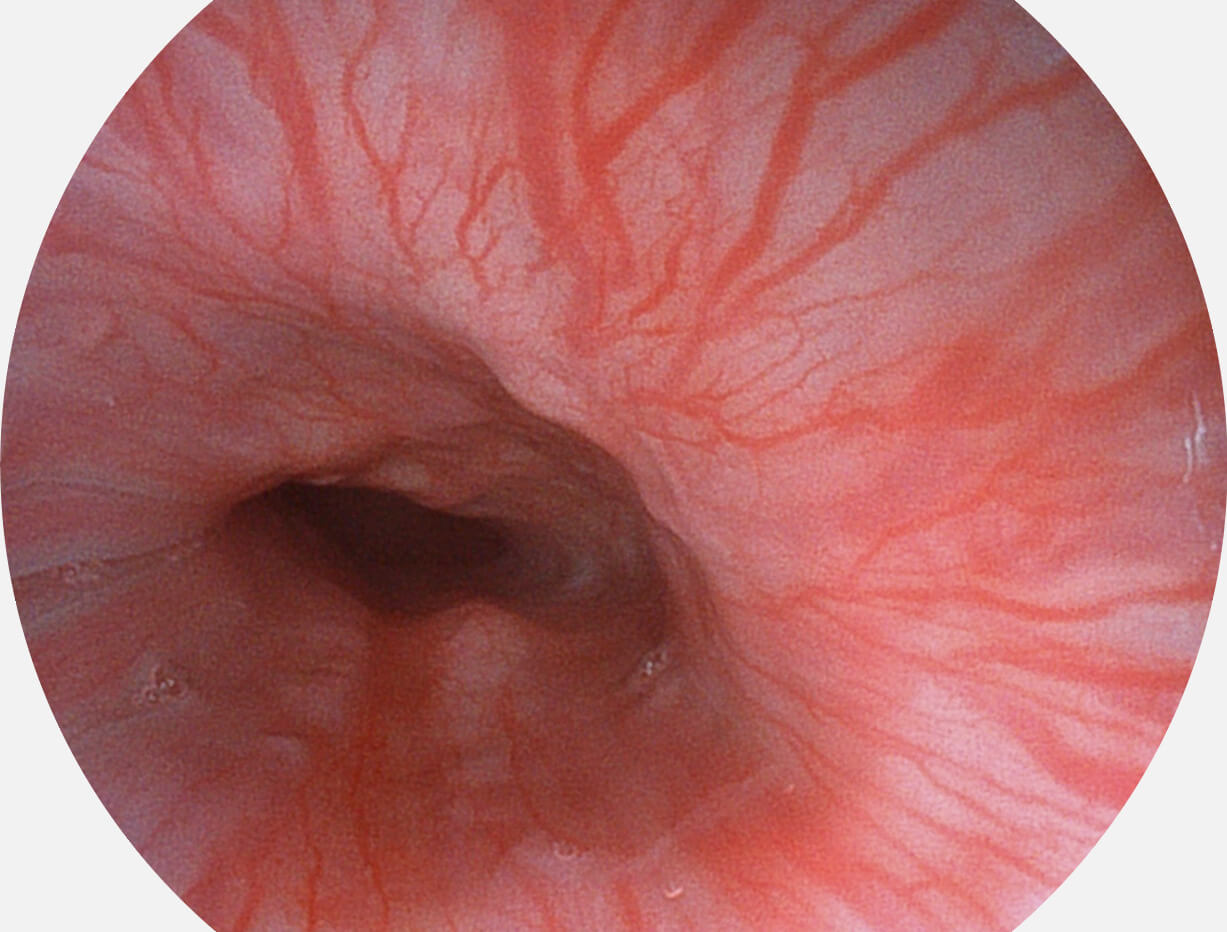

Versatile Intelligent Staining Technology, VIST

强调浅层黏膜结构的同时,保证照明亮度和提升浅层微血管与中层血管颜色对比度,病变边界更清晰。

白光图像

VIST图像

采用光路合束技术,光谱自由度高,实现了更丰富的照明模式,染色模式SFI及VIST,从远景到近景,助力消化道早期疾病诊断。